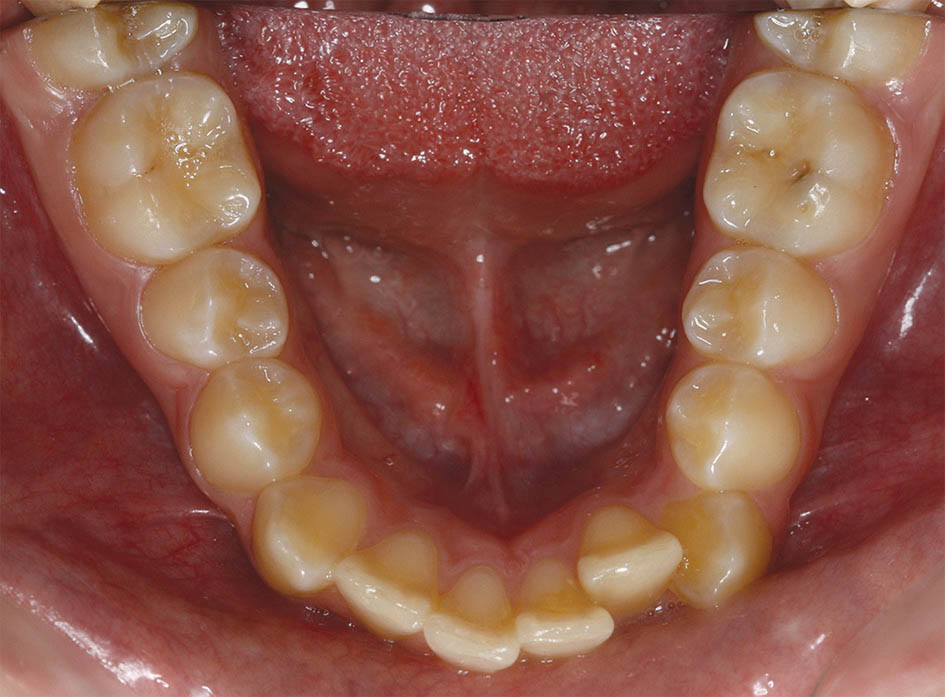

شکل 68-3 : قوس پایین در ابتدای درمان